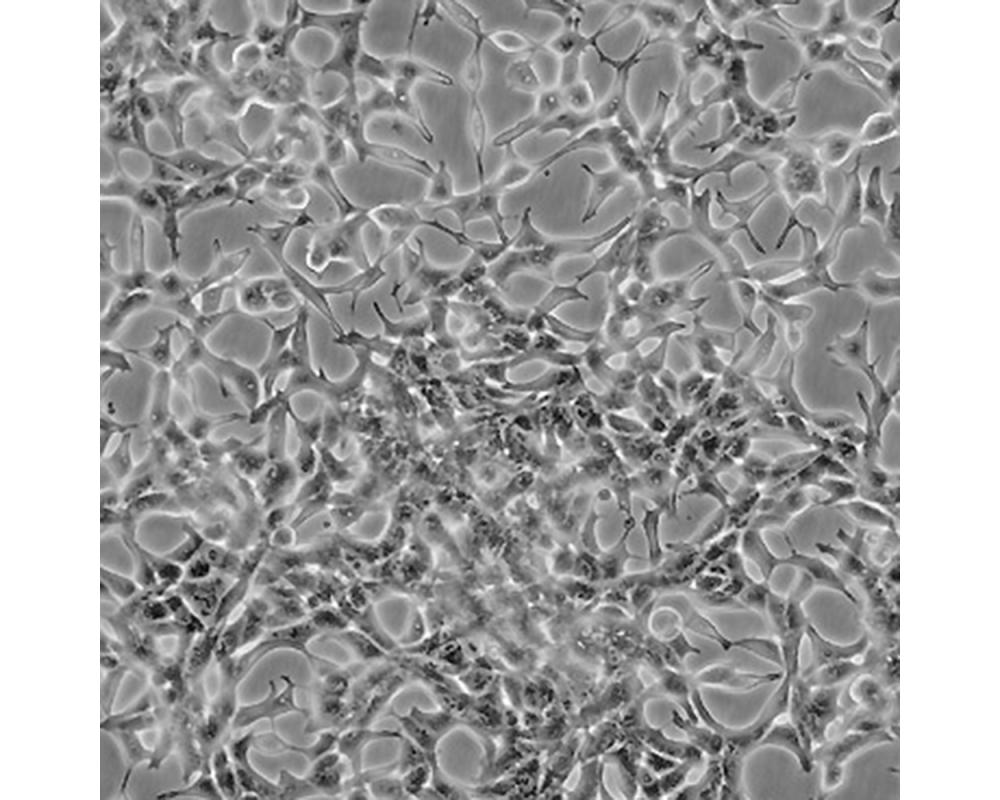

LNCaP clone FGC [LNCaP.FGC]

人前列腺癌細胞

前列腺癌;左鎖骨上淋巴結(jié)轉(zhuǎn)移;男性

形態(tài)特征

上皮細胞

生長特性

人前列腺癌細胞LNCaP克隆FGC是從一位50歲白人男性(血型B+)的左鎖骨淋巴結(jié)針刺活檢中分離,該患者經(jīng)確診為前列腺癌轉(zhuǎn)移。 這株細胞對5-α-二氫睪酮(生長調(diào)節(jié)子和酸性磷酸脂酶產(chǎn)物)有響應。 這株細胞并不形成一致的單層,而是形成集落,在傳代時可以用滴管反復吹吸打碎。 它們僅僅輕輕地吸附在基底上,不形成匯合,很快使培養(yǎng)基變酸。 生長很慢。 傳代后48小時內(nèi)不應擾動。 當培養(yǎng)瓶封包后,多數(shù)細胞從培養(yǎng)瓶底分離,懸浮在培養(yǎng)基中。 收到后,在通常培養(yǎng)單層細胞的條件下培養(yǎng)24到48小時,以合細胞再貼壁。